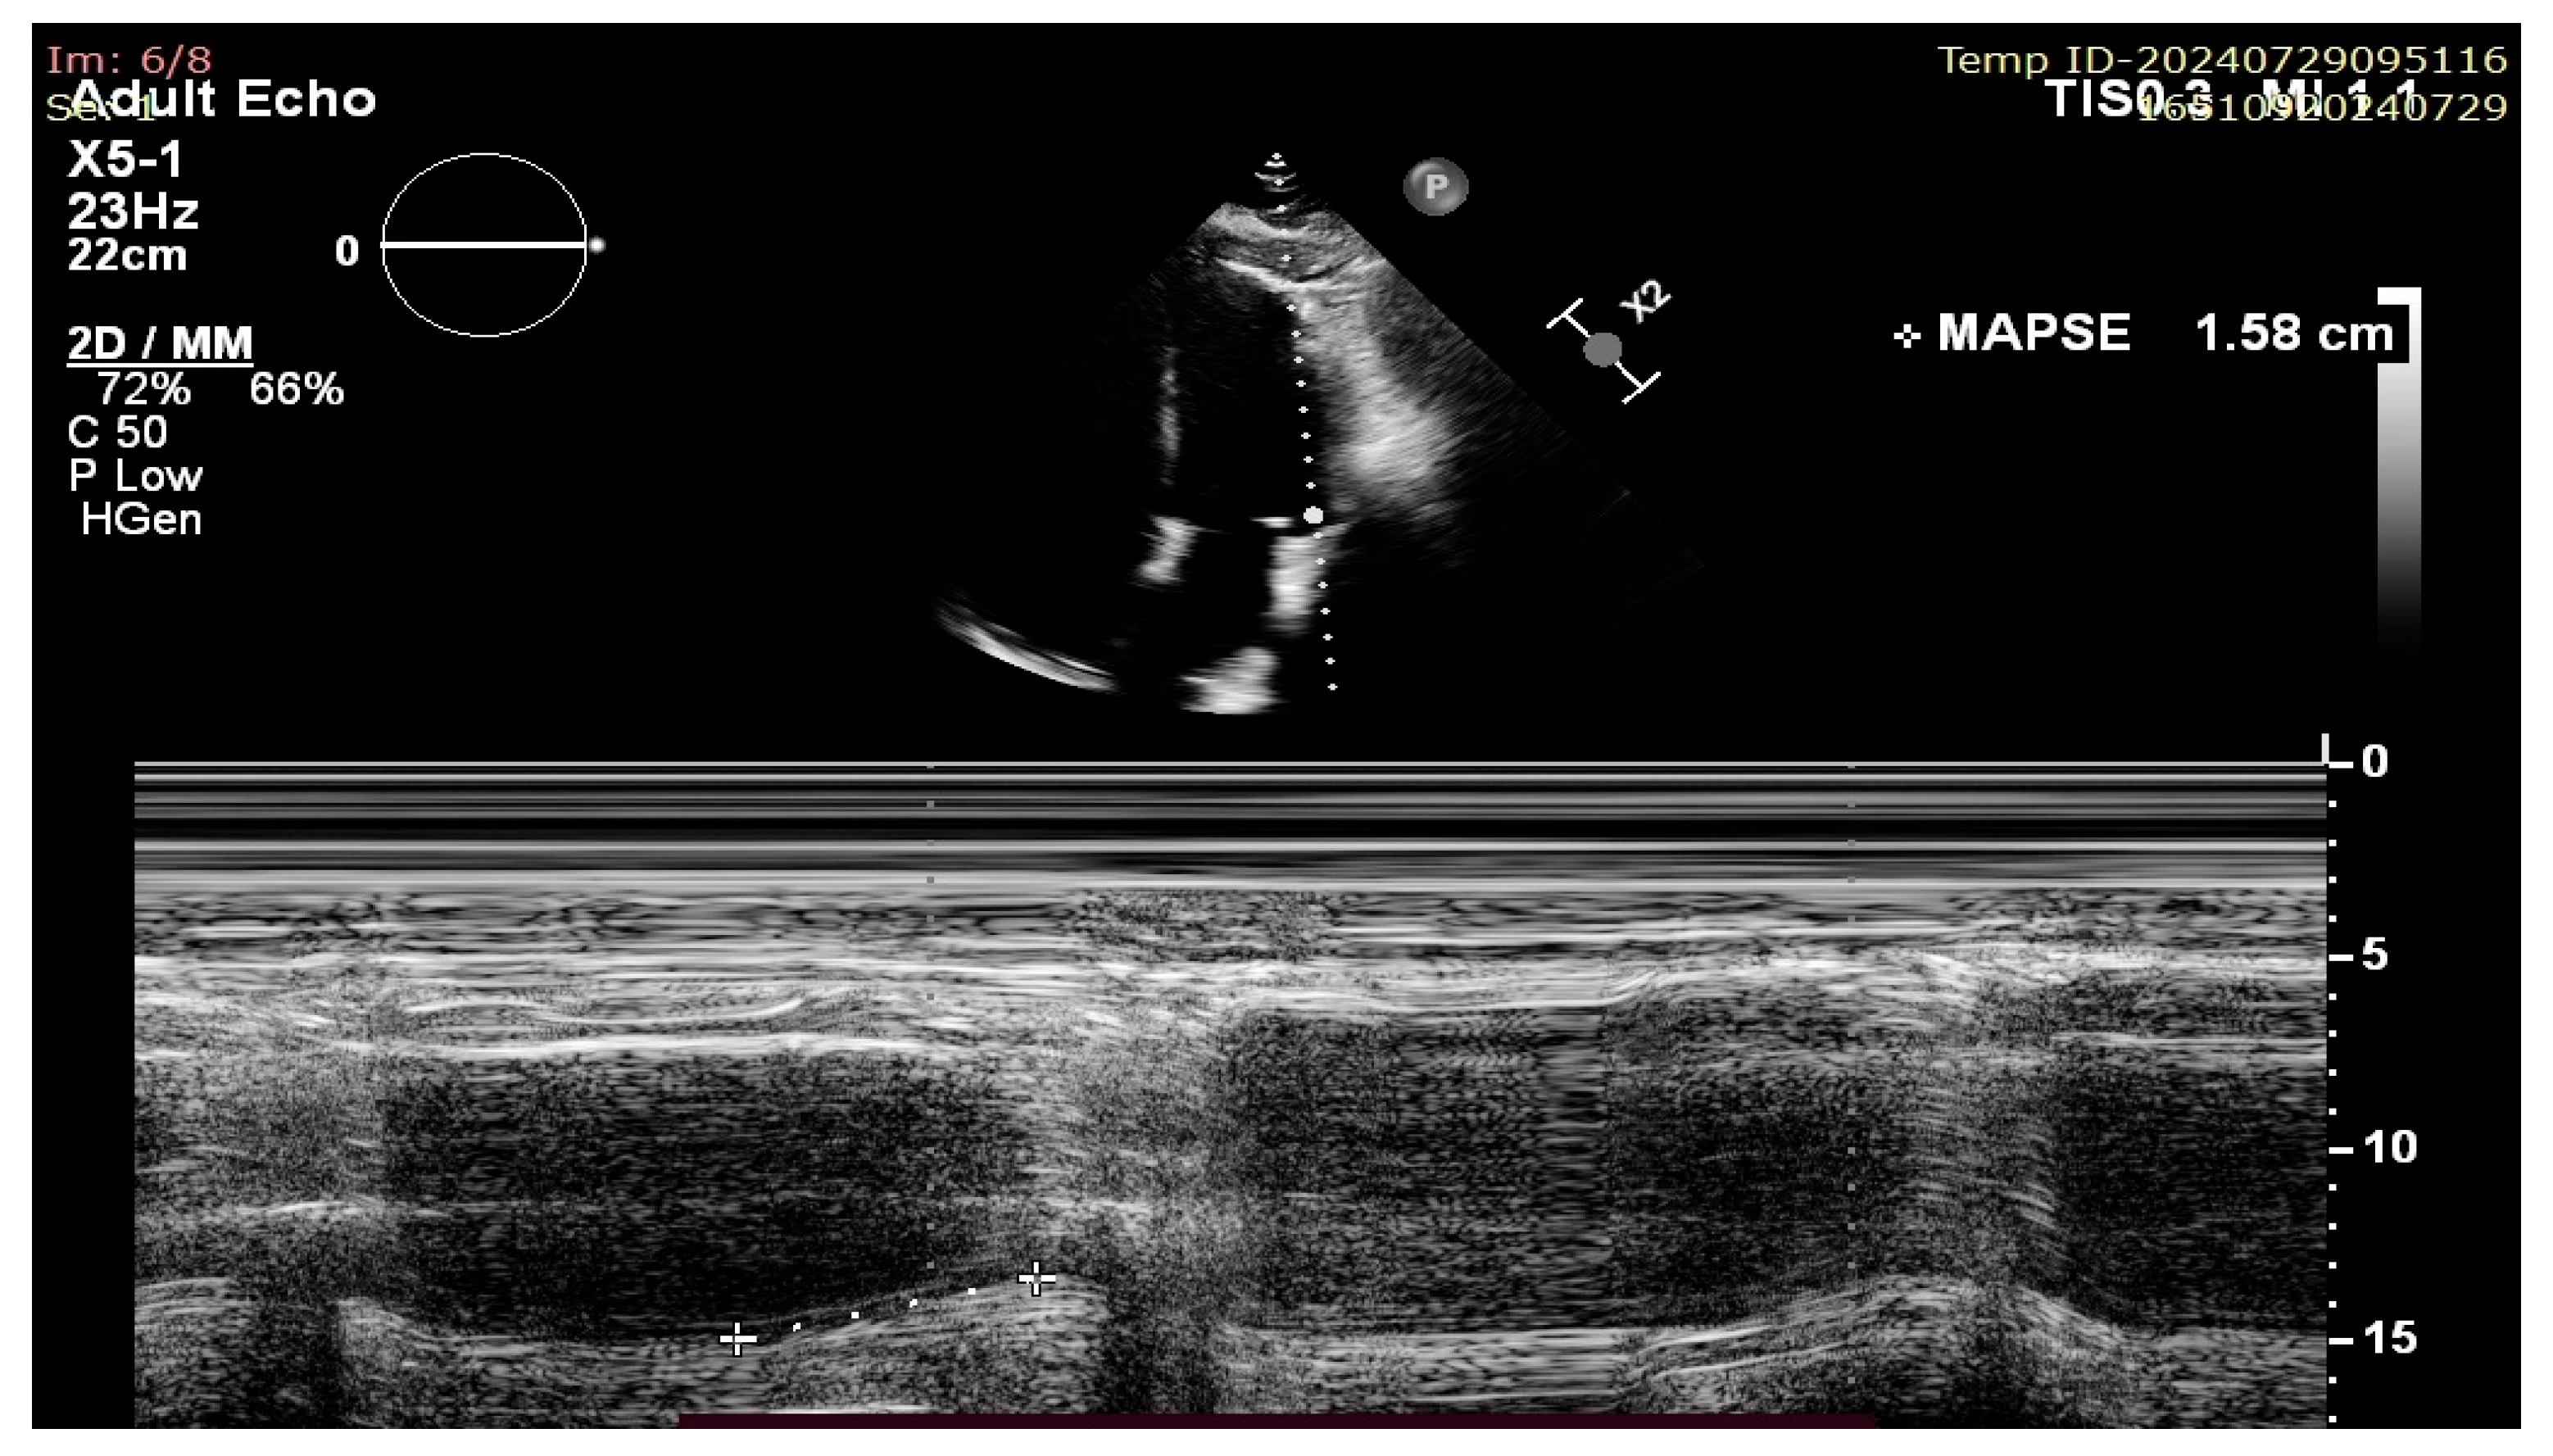

Mitral Annular Plane Systolic Excursion (MAPSE): A Review of a Simple and Forgotten Parameter for Assessing Left Ventricle Function